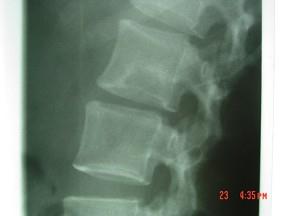

问题 男,33岁,有午后发热,夜间盗汗等,腰部疼痛,活动时加重,休息后减轻,请结合所提供图像,选择最佳答案 ( )

选项 A、骨巨细胞瘤 B、骨髓瘤 C、腰椎骨转移 D、腰椎退行性变 E、腰椎结核

答案 E